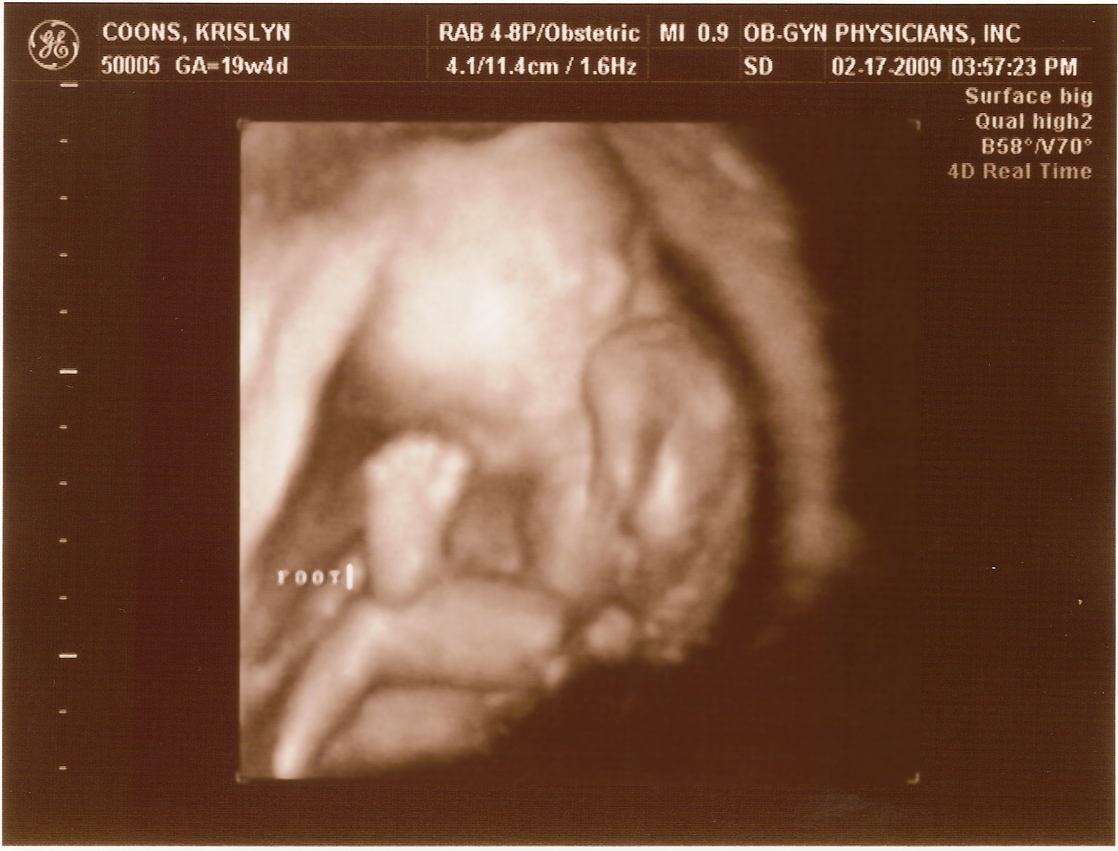

2.17.2009

First ultrasound! The baby measures right on target and appears to be developing normally. All looked and sounded great. Krislyn is finally gaining some baby weight too!

20 weeks -

20 weeks